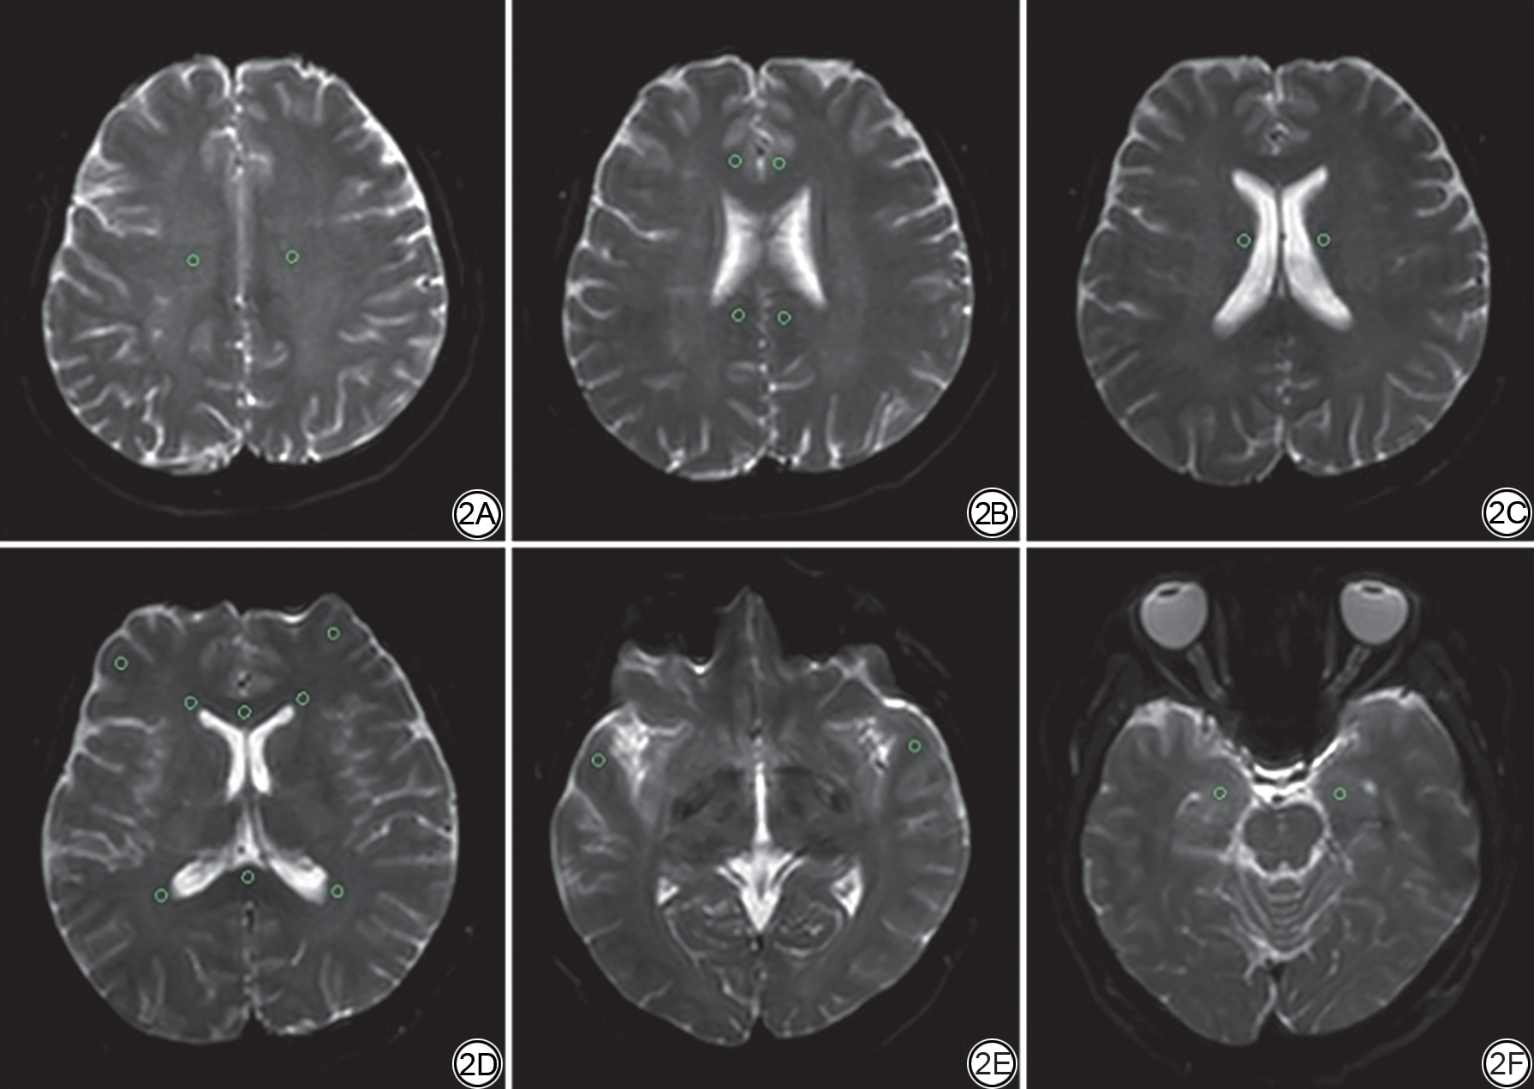

数据重建及测量在Philips后处理工作站“IntelliSpace Portal(ISP)”version 6 (Philips Medical Systems)上进行。数据测量前利用Philips ISP工作站内置配准模块(如“Image Registration”)将ASL与DTI图像进行融合,从而确保ROI在CBF图、FA图和ADC图解剖位置一致。参考既往文献[3, 12, 21, 22, 23],两位经验丰富的影像医师依据T2WI图像独立双盲选取位置、大小、形态一致的感兴趣区(region of interest, ROI),包括双侧颞叶皮层下、额叶皮层下、半卵圆中心、放射冠、侧脑室前角及侧脑室三角区、扣带回、海马以及胼胝体(图2),ROI大小约8~10 mm2;各参数值最终定义为两位医师所有测量值的平均值。

图2  以健康对照(HC)组为代表的图像中感兴趣区(ROI)所在位置。2A:半卵圆中心;2B:扣带回;2C:放射冠;2D:额叶、胼胝体、侧脑室前角及侧脑室三角区;2E:颞叶;2F:海马。

Fig. 2  The region of interest (ROI) locations in images represented by the healthy control (HC) group. 2A: Semi-oval center; 2B: Cingulate gyrus; 2C: Radioactive crown; 2D: Frontal lobe, corpus callosum, anterior horn of lateral ventricle and triangular area of lateral ventricle; 2E: Temporal lobe; 2F: Hippocampus.